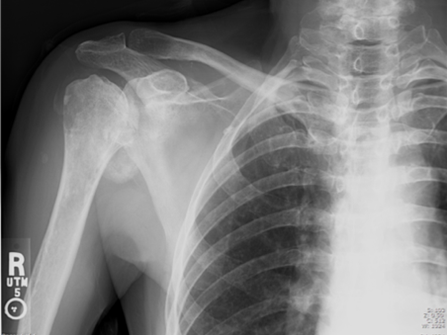

Calcific Bursitis

Milwaukee Shoulder